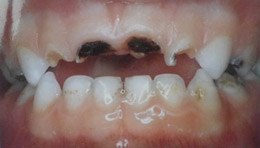

Τερηδόνα βρεφικής και νηπιακής ηλικίας ή τερηδόνα θηλασμού

Η τερηδόνα βρεφικής και νηπιακής ηλικίας εμφανίζεται σε μικρά παιδιά ηλικίας 2 έως 5 ετών, τα οποία έχουν τερηδονισμένα ένα ή και περισσότερα νεογιλά δόντια. Η τερηδόνα αυτής της μορφής οφείλεται σε λάθος τρόπο διατροφής του παιδιού και μπορεί να εξελιχθεί γρήγορα και σε μεγάλη έκταση επηρεάζοντας το σύνολο το δοντιών που βρίσκονται στο στόμα.

Η κυριότερη αιτία εμφάνισης της τερηδόνας αυτής της μορφής είναι το τάισμα με το μπιμπερό ενώ το παιδί κοιμάται. Κατά τη διάρκεια του ύπνου η ποσότητα του σάλιου μειώνεται και το γάλα, ανεξάρτητα αν περιέχει ή όχι ζάχαρη, παραμένει πάνω στα δόντια και προκαλεί τερηδόνα. Ακόμη και το μητρικό γάλα μπορεί να έχει τις ίδιες συνέπειες, εφόσον το παιδί θηλάζει κατά βούληση κατά τη διάρκεια της νύχτας.